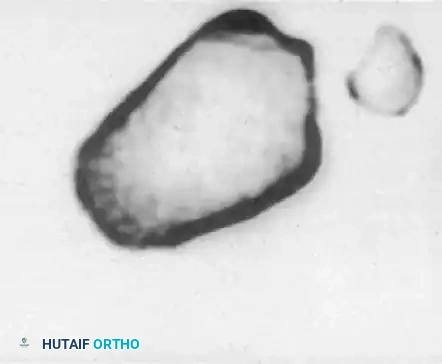

Dislocations of the PTFJ usually occur with the knee flexed and the ankle inverted and plantarflexed. This tension on the lateral collateral ligament and biceps femoris tendon can avulse or displace the fibular head.

FIGURE 60-6: A and B, Acute dislocation of the proximal tibiofibular joint. C and D, After closed reduction. Note the distinct change in the position of the fibular head relative to the lateral tibial plateau in both orthogonal views.